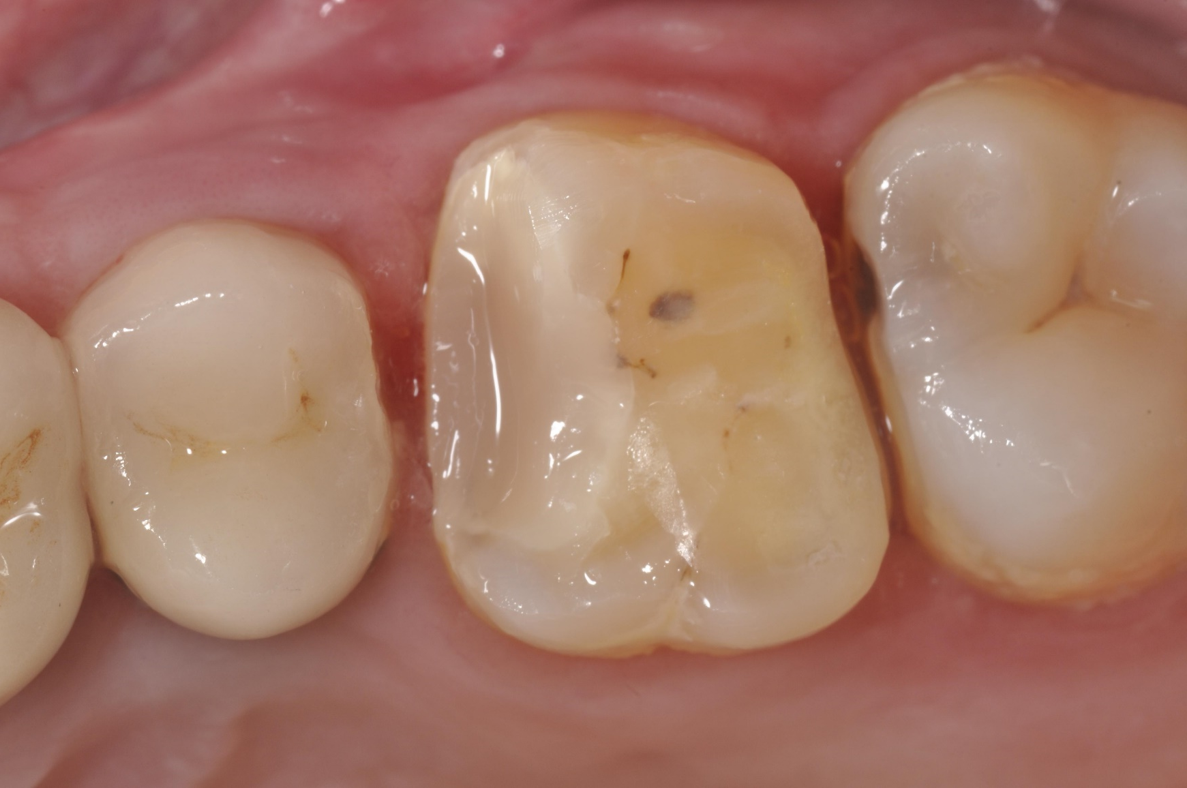

陶瓷冠塊體口內黏著

治療後口內照

當蛀牙破壞程度大,陶瓷冠塊體是根據蛀牙的窩洞量身訂做,不管是顏色、精密度都是最佳的選擇,因此是非常美觀與持久的填補窩洞材料與技術